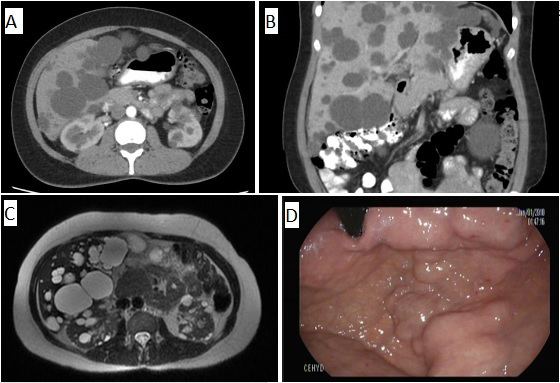

50-year-old asymptomatic woman, with a history of hyperprolactinemia secondary to pituitary microadenoma, and infertility. In medical check-up they find hepatomegaly, so they request ultrasound, with finding of PLD. CT and abdominal resonance confirm the diagnosis (Figures 1-C). Digestive endoscopy shows extrinsic compression (Figure 1D). With a normal renal and hepatic profile, it is decided jointly with urology, nephrology and hepatology, expectant management and periodic control.

Figure 1 A-B Axial and coronal section, in which multiple hepatic cysts are observed. C. especially renal cysts are observed. D. In the retrovision of the upper digestive endoscopy, an image is observed that may suggest gastric varices, but which actually corresponds to the extrinsic compression caused by hepatic cysts.